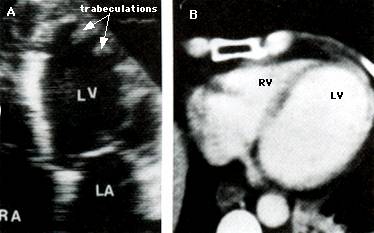

Ingrosarea peretelui VS asemanatoare CMH apare la copii (si la unii adulti) cu alte boli : sindromul Noonan, miopatiile mitocondriale, ataxia Friedreich, tulburari metabolice, boala Anderson-Fabry (deficienta legata de cromozomul X a enzimei lizozomale alfa-galactozidaza), noncompactarea VS si amiloidoza cardiaca.

Confirma diagnosticul de CMH, cuantifica elementele morfologice - distributia hipertrofiei, functionale - hipercontractilitatea VS si hemodinamice - gradientul intraventricular.

Caracterele ecocardiografice sunt :

Maron si colaboratorii descriu 4 tipuri de hipertrofie in CMH :

tipul I - hipertrofie localizata in portiunea anterioara a SIV

tipul II - hipertrofia intereseaza tot SIV, peretele liber este normal

tipul III - hipertrofia cuprinde SIV si peretele anterior, peretele inferior este normal

tipul IV - hipertrofie localizata in alte parti ale peretelui liber, nu cuprinde portiunea anterioara a SIV dar poate afecta alte zone (peretele anterior, peretele lateral, portiunea posterioara a SIV, peretele posterior sau apexul VS in forma apicala).

Cea mai frecventa este CMH tip I (in 90 % din cazuri), dar se poate intalni si hipertrofia simetrica de perete.